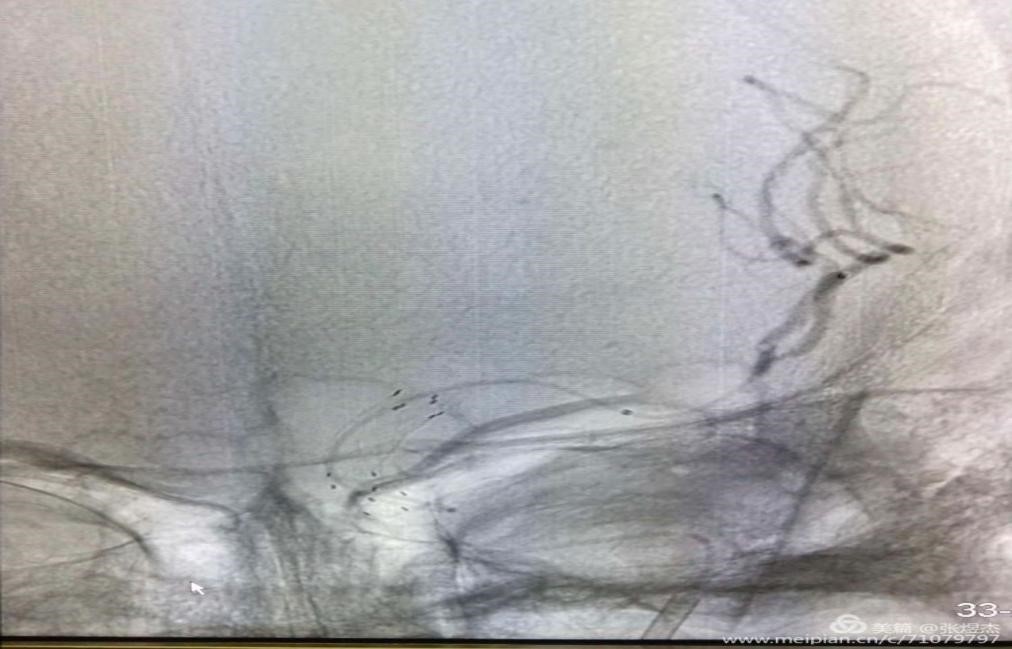

然后就到了支架拉栓的步骤了,沿微导管置入4mm取栓支架,到达病变位置后,后撤微导管缓慢释放支架,使血栓位于支架的前1/3位置,当支架完全打开与血栓充分接触后,这时缓慢回收支架入导引导管,完成取栓。再次造影刚才不通的上干血管就开通了,我们可以看到上下两干血管,复通的上干存在原位狭窄(箭头所指),这也是为什么栓子卡在这里的原因。

将取出来的血栓从支架上取下,摊开,大约是1cm的长度。